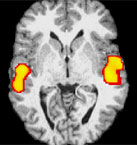

MRI-scan hersenenDeze verklaring is gebaseerd op ander onderzoek, waarbij op basis van hersenscans blijkt dat ouderen moeite hebben met het terzijde schuiven van onbelangrijke impulsen. Hierdoor raken ze snel afgeleid en zijn ze slecht in het uitvoeren van meerdere taken tegelijkertijd. Mensen tussen de twintig en dertig jaar kunnen daarentegen juist optimaal irrelevante hersengebieden uitschakelen en relevante gebieden inschakelen. Van meertaligheid was het al twintig jaar bekend dat dit gepaard ging met verbeterde capaciteiten om irrelevante informatie te blokkeren. Gamers vertoonden in de tests van Ellen Bailystok dezelfde patronen als tweetaligen, wat erop wijst dat zij een soortgelijke verbetering van cognitieve aandachtsdistributie hebben ontwikkeld. Dit effect zou een blijvend karakter kunnen hebben, alhoewel enige relativering op zijn plaats is. De wereld wordt namelijk per generatie complexer, waardoor een nu opgedane voorsprong relatief klein is in vergelijking met de cognitieve vooruitgang die volgende generaties zullen boeken vanwege de wereld om hen heen.